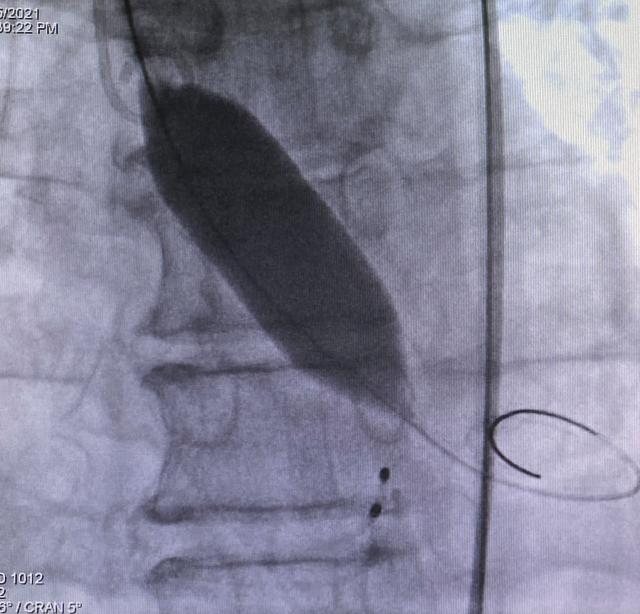

佘飞医师及薛亚军医师反复阅读超声及CT评估结果,与张萍教授、王伟民教授、吴永健教授讨论病情后,综合评估结果,决定行TAVR 手术,采用22mm球囊预扩张主动脉瓣,植入26mm Venus-A 瓣膜。通过充分的术前评估与准备,与患者家属反复沟通、告知病情以及相关风险,最终获得家属的手术同意。

4月15日上午在吴永健教授指导下、心脏内科介入团队密切协作,成功为患者完成经皮主动脉瓣置换术,瓣膜位置良好,无瓣周漏、无跨瓣压差。术后患者血流动力学稳定,呼吸功能良好,达到撤机标准,随后顺利脱机,安全返回监护病房。